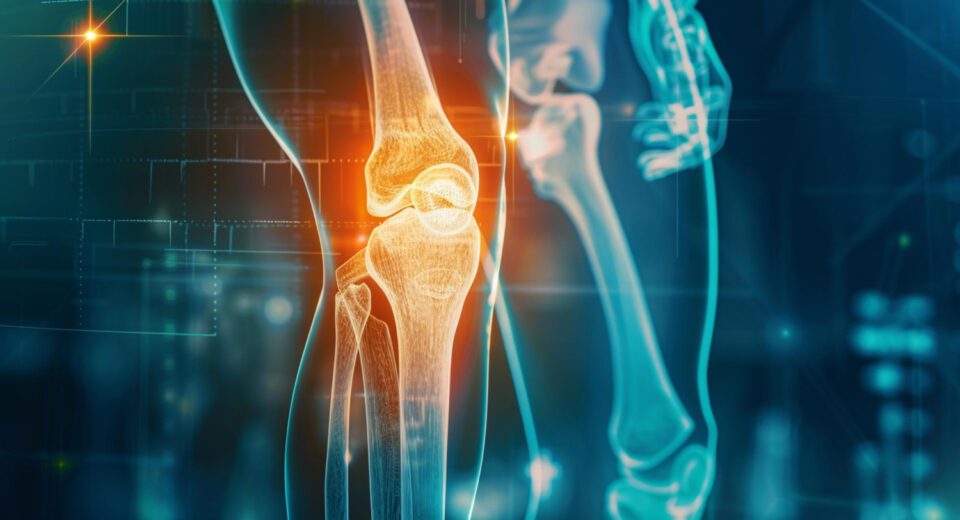

Naučnici sa Stenforda otkrili način da se obnovi hrskavica: kraj zamene kolena i kuka?

Zamena kolena i kuka je industrija vredna više od 65 milijardi dolara godišnje, zasnovana na jednoj dugogodišnjoj pretpostavci: kada se zglobna hrskavica istroši, telo ne može da je obnovi.Novo istraživanje naučnika sa Univerziteta Stanford dovodi tu pretpostavku ozbiljno u pitanje. Njihovi rezultati ukazuju da je moguće pokrenuti prirodnu regeneraciju hrskavice, čak i kod starijih organizama […]